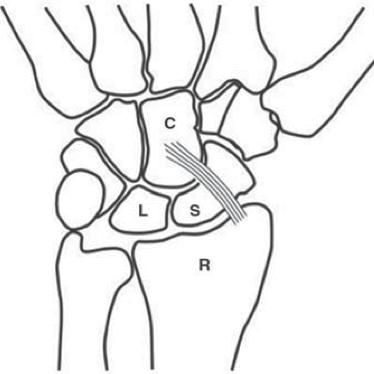

앞쪽의 경우 Radius 와 Ulna 와 수근골을 연결하는 단단한 인대들이 구성되어 있고

RSC 는 손목 안정화에 주요한 구조물 입니다. (Proximal row carpectomy 후에도 살리는 구조물 입니다.)

없으면 척골쪽으로 수근골들이 모두 빠지기 쉽습니다.